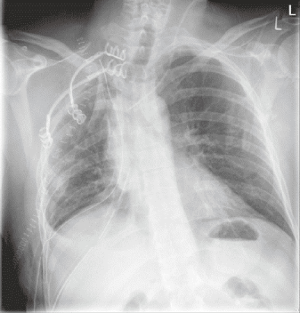

In lung cancer surgery, chest wall reconstruction may be required after chest wall resection performed due to direct invasion of the tumour into the chest wall. If the tumour is located in the lung apex (Figure 1) causing Pancoast syndrome, reconstruction is rarely indicated, however it may be necessary to prevent dropping of the shoulder and maintaining the shape of the chest wall close to normal. In these cases, the metal bars may be used to recreate the anatomically acceptable shape of the chest wall. StraTos bars (MedXpert, Germany) could be quite useful, because it is possible to bend them to the required shape and to secure them normally or in the invert position if required (Figure 2). The repair of the first rib is usually not possible and not usually performed.